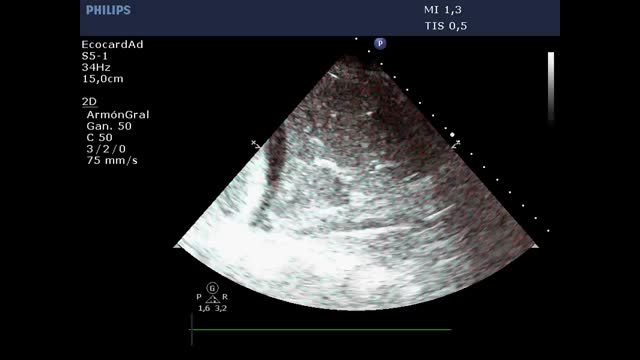

Utilidad de la ecografía en el weaning de la ventilación mecánicaEl fracaso del weaning o la reintubación precoz se asocian a una elevada morbimortalidad40, por lo que una evaluación dirigida al diagnóstico precoz de las causas que dificultan la desconexión de la ventilación mejorará el pronóstico de los pacientes. Las principales causas de fracaso del weaning pueden resumirse en tres grandes grupos: respiratorias, cardíacas y neuromusculares41. En ese sentido, el estudio mediante ecografía del corazón, los pulmones y la musculatura respiratoria puede ayudar a comprender el proceso fisiopatológico por el que un paciente fracasa en el proceso de weaning (fig. 6 y algoritmo 3).

Principales exploraciones ecográficas utilizadas para el diagnóstico de la causa del fracaso de la retirada de la ventilación mecánica. Se dividen en exploraciones que precisan un conocimiento básico de ecografía y exploraciones que precisan un grado avanzado de formación en ecografía. A)Ecografía pulmonar con detección de un aumento ≥6 líneasB durante la prueba de respiración espontánea para el diagnóstico de edema pulmonar inducido por el weaning (WIPO). B)Ecografía cardiaca, plano apical 4cámaras para estudio de la función sistólica del ventrículo izquierdo y el estudio de alteraciones estructurales del mismo (hipertrofia, dilatación, insuficiencia mitral grave). C)Estudio del diafragma mediante la excursión, en imagen en 2dimensiones (ver vídeo del material electrónico suplementario). D)Estudio del diafragma mediante la excursión, imagen en modoM; obsérvese la onda generada por el desplazamiento diafragmático con los movimientos respiratorios (una excursión <10mm se considera patológica). E-G)Imágenes utilizadas para el cálculo del Lung Ultrasound Score (LUS) tal y como se describe en el texto. H)Estudio de la función diastólica, imagen de Doppler pulsado del flujo transmitral mostrando las ondas de llenado temprano (E, flecha blanca) y tardío (A, flecha roja). I)Estudio de función diastólica, imagen de Doppler tisular del anillo mitral lateral mostrando la ondae’ (flecha blanca). J)Imagen en modo bidimensional del diafragma en la zona de aposición sobre el noveno espacio intercostal; el diafragma es la estructura localizada ente las dos líneas hiperecogénicas identificadas con la flechas (superior pleura, inferior diafragma, vídeo del material electrónico suplementario). K)Imagen en modoM para el estudio de la fracción de engrosamiento diafragmática identificando el grosor máximo en la inspiración y el mínimo en la espiración.

El estudio mediante ecocardiografía de los parámetros de función diastólica (llenado ventricular y relajación miocárdica) y presiones de llenado del ventrículo izquierdo juega un papel primordial en la evaluación del fracaso del weaning de la ventilación mecánica45. El estudio del flujo transmitral mediante Doppler pulsado y de la velocidad de desplazamiento del anillo mitral mediante Doppler tisular permite identificar las ondasE ye’, respectivamente (fig. 6). La relación entre las ondas E/e’ se ha sugerido como una medida para estimar la presión de llenado del ventrículo izquierdo46, si bien los resultados son contradictorios47.